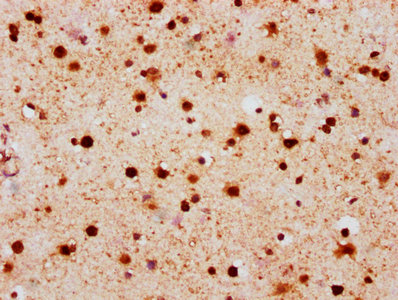

IHC image of CSB-RA010097A139phHU diluted at 1:100 and staining in paraffin-embedded human brain tissue performed on a Leica BondTM system. After dewaxing and hydration, antigen retrieval was mediated by high pressure in a citrate buffer (pH 6.0). Section was blocked with 10% normal goat serum 30min at RT. Then primary antibody (1% BSA) was incubated at 4°C overnight. The primary is detected by a biotinylated secondary antibody and visualized using an HRP conjugated SP system.

Application Recommended Dilution WB 1:500-1:5000 IHC 1:50-1:200 -